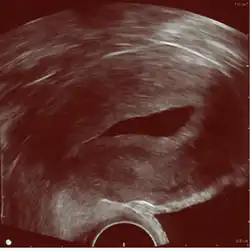

Device for both vaginal ultrasonography and abdominal ultrasonography

The examination can be performed by transabdominal ultrasonography, generally with a full bladder which acts as an acoustic window to achieve better visualization of pelvis organs, or by transvaginal ultrasonography with a specifically designed vaginal transducer. Transvaginal imaging utilizes a higher frequency imaging, which gives better resolution of the ovaries, uterus and endometrium (the fallopian tubes are generally not seen unless distended), but is limited to depth of image penetration, whereas larger lesions reaching into the abdomen are better seen transabdominally. Having a full bladder for the transabdominal portion of the exam is helpful because sound travels through fluid with less attenuation to better visualize the uterus and ovaries which lies posteriorly to the bladder. The procedure is by definition invasive when performed transvaginally. Scans are performed by health care professionals called sonographers, or gynecologists trained in ultrasound.